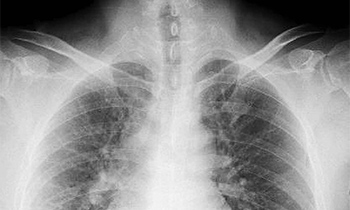

胸部エックス線検査

エックス線を使って胸の内部の状態を画像化する検査です。肺はもちろん、心臓、気管支などに問題がないかを確認でき、肺がん、肺炎、肺結核、気胸、心臓肥大といった病気の早期発見に役立ちます。